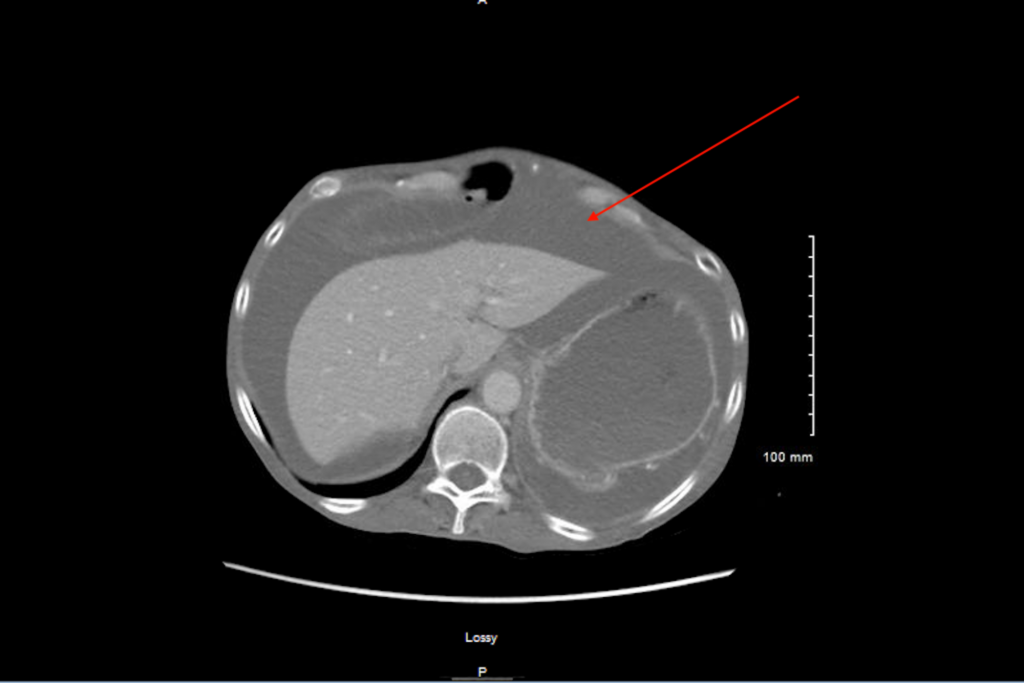

Η διάγνωση γίνεται με υπερηχογράφημα, αξονική και μαγνητική τομογραφία.

Γίνεται διαγνωστική παρακέντηση, λαπαροσκόπηση, υπέρηχος, μαγνητική τομογραφία, αξονική τομογραφία

Βαθμός 1: ήπιος, ορατός μόνο σε υπερήχους και CT

Βαθμός 2: ανιχνεύσιμος με κλινική εξέταση

Βαθμός 3: άμεσα ορατός, και επιβεβαιώνεται με τη δοκιμή υγρού κύματος